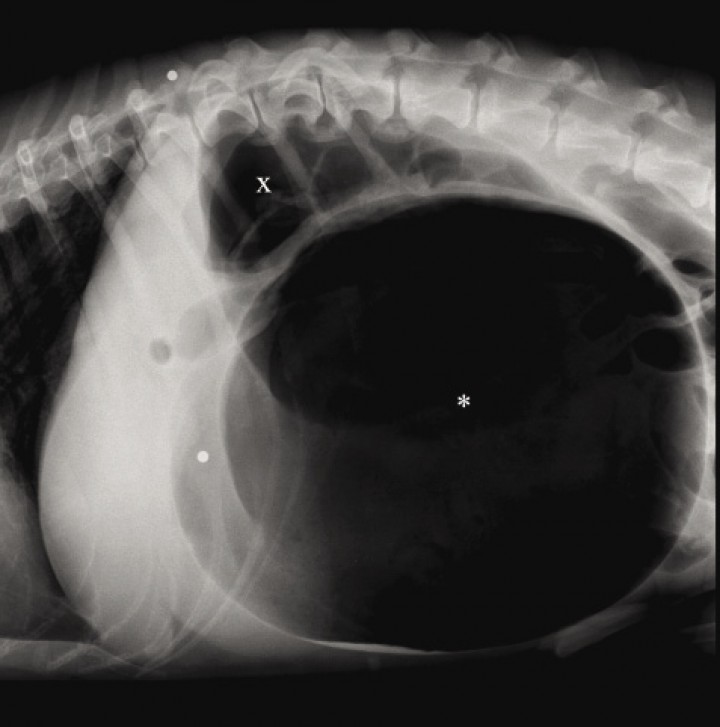

La radiografía es de utilidad para confirmar y diferenciar la dilatación gástrica de la DVG. Antes de realizar el examen radiográfico se debe descomprimir el abdomen por medio de un trocar o una sonda orogástrica.[ Monnet E. Gastric dilatation-volvulus syndrome in dogs. Vet Clin Small Anim Pract 2003; 33: 987-1005. [PubMed] , Cornell K. Gastric dilatation and volvulus. En Tobias KM, Johnston SA (ed): Veterinary Surgery Small Animal. Vol. 2. St. Louis, Missouri, Elsevier Saunders, 2012; 1508-1510. ] La radiografía debe realizarse en decúbito lateral derecho. Cuando el vólvulo se produce por la rotación sobre el eje transversal del estómago, se observa una imagen de bicompartimentación debido a la acumulación de aire en el píloro y el fundus (Fig. 5).[ Monnet E. Gastric dilatation-volvulus syndrome in dogs. Vet Clin Small Anim Pract 2003; 33: 987-1005. [PubMed] , Cornell K. Gastric dilatation and volvulus. En Tobias KM, Johnston SA (ed): Veterinary Surgery Small Animal. Vol. 2. St. Louis, Missouri, Elsevier Saunders, 2012; 1508-1510. ] Cuando la DVG es debida al giro sobre el eje longitudinal, se puede visualizar el estómago desplazado caudalmente y el fundus localizado en el lado derecho (Fig. 6).[ Carrillo JD, Escobar M, Soler M, Agut A. ¿Cuál es tu diagnóstico?. Clin Vet Peq Anim 2015; 35: 123-125. ]

<p>Radiografía lateral derecha de la cavidad abdominal craneal en un perro con DVG donde puede visualizarse una gran distensión gástrica y el signo de bicompartimentación, indicativo de vólvulo gástrico sobre el eje transversal, observándose el antro pilórico dorsalmente (x) y el fundus ventral (*).</p>

Radiografía lateral derecha de la cavidad abdominal craneal en un perro con DVG donde puede visualizarse una gran distensión gástrica y el signo de bicompartimentación, indicativo de vólvulo gástrico sobre el eje transversal, observándose el antro pilórico dorsalmente (x) y el fundus ventral (*).